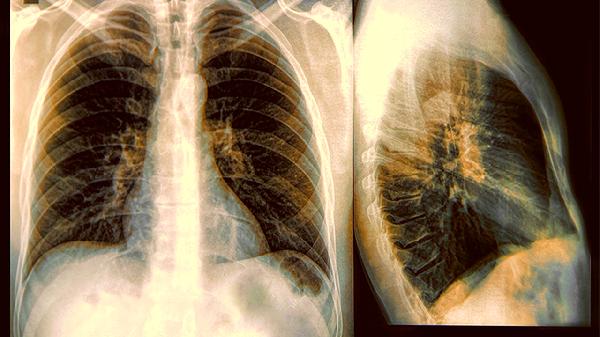

当咳嗽出现铁锈色痰或血丝,说明炎症已突破粘膜屏障。这个阶段肺部CT检查可能会发现早期癌前病变。